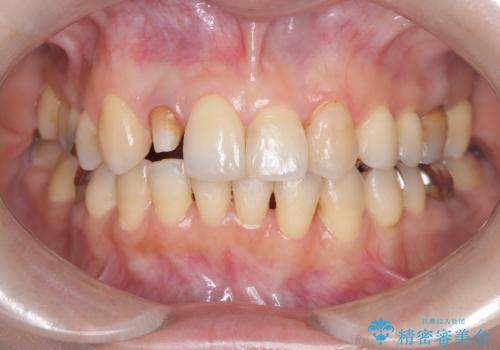

- 「前歯の見た目が気になる」を主訴に来院された患者様です。

失活歯による歯の変色とCR(コンポジットレジン)の劣化による審美不良でした。

オールセラミッククラウンで治療し見た目の改善を行いました。

まず劣化したCRと虫歯を除去した後、仮歯に置き換えました。歯のマージンラインを綺麗に削り光沢が出るまで研磨した後にオールセラミッククラウンの型取りを行っています。